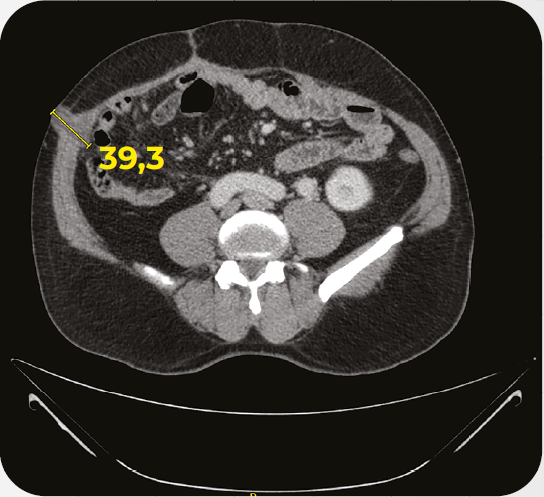

Caso clínico: paciente com CRC MSI-H O Caso clínico em questão, traz detalhes sobre o tratamento em 1L de pacientes com câncer colorretal metastático com deficiência de enzimas do reparo (dMMR)/alto nível de instabilidade de microssatélites (MSI-H).